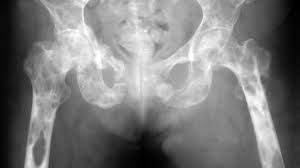

Radiation treatment every now and again makes patients feel tired and lose their hankering, and it can make the skin over the treated domain continuously tricky and bothered. Inverse manifestations depend upon the bit of the body that was managed. For example, radiation to the pelvic area may make camouflage of the bone marrow and lead lessened platelet counts. This is in light of the fact that half of the body's bone marrow is found in the pelvic bones. Radiation to the pelvic zone can in like manner impact the lower stomach related tract, causing signs, for instance, detachment of the guts, fits and, in exceptional cases, kicking the bucket. It can in like manner impact the regenerative organs.